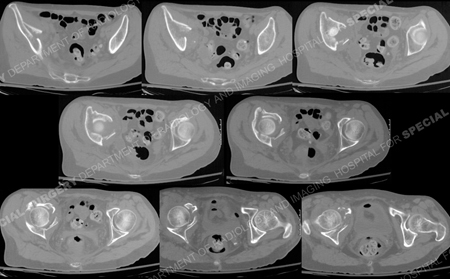

CT scan images further delineating the fracture pattern.